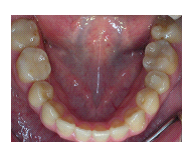

22歲男性病人,五年前齒顎矯正醫師,將其嚴重蛀牙的右下顎第一大臼齒拔除,如圖2A所示。再將第二大臼齒以矯正力量拉至第一大臼齒的位置,矯正結束後,再次評估,認為此第二大臼齒蛀牙太嚴重,仍無法保留,決定予以拔除,如圖2B所示。同時將右上顎阻生智齒,如圖2C,移植過來。如圖2D、2E為術後一個月之X光片,由於病人尚年輕,因此暫不予以根管治療,觀察智齒是否可保留牙髓活性。圖2F為術後一年半的情形,智齒牙根尖周圍的骨頭已全部再生回來,並無牙根黏連情形,而且牙髓仍保持其活性,牙周情況良好,咬合正常。

圖2A

圖2B